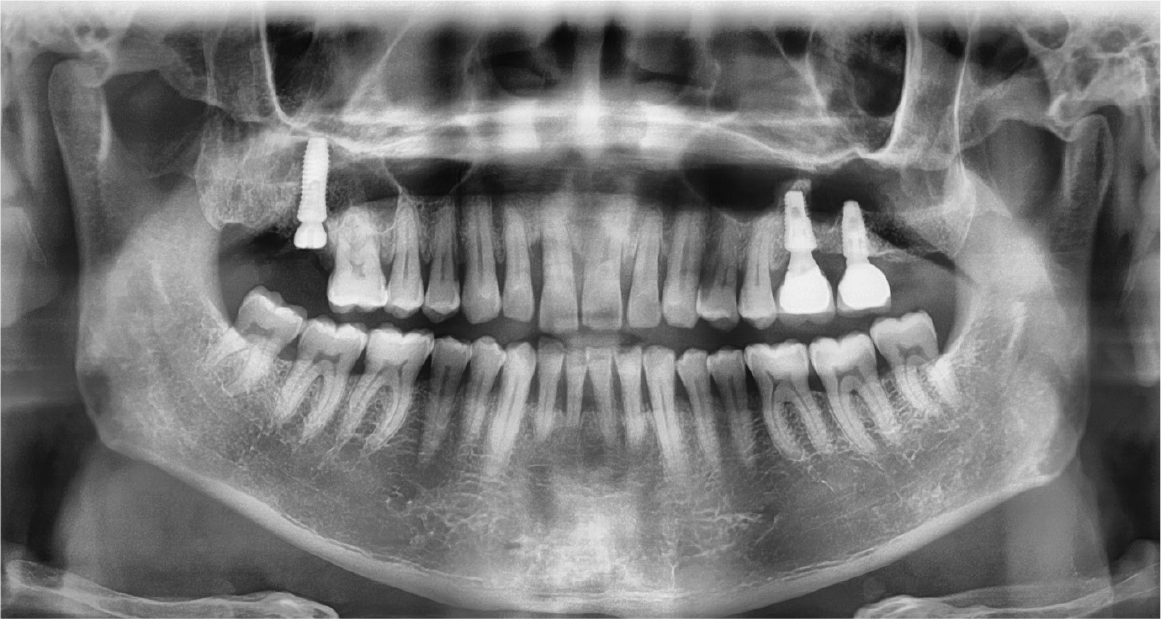

The right maxillary second and third molars were extracted. A lateral bony window was prepared, and the sinus membrane was thoroughly lifted from the sinus floor with bony window lifted upward and inward. But the mesial aspect of the lifted sinus membrane was perforated (about 4 – 5 mm). A collagen wound dressing (Colla-tape®; Zimmer Dental Carlsbad, CA, USA) was used for the repair of the sinus membrane perforation (Fig. 2). Alloplastic bone-grafting material (A-oss®; Osstem implant Co., Seoul, Korea) was packed and the implant placement (Superline®; Dentium implant Co., Seoul, Korea) was performed (Fig. 3). After 7 days, the patient had pain, nasal discharge and foul odor on the right paranasal area. Under local anesthesia, the flap was elevated. The infected bone material, fixture, collagen wound dressing and infected tissue were removed (Fig. 4). Sinus irrigation was performed for about 5 minutes, until the foul odor and the blockage of ostium disappeared. During this procedure, the size of perforation got bigger by about 1 cm.

After the stuffy nose on the right side was completely gone, the bony window was extended anteriorly and the sinus membrane around perforated area was lifted. The perforated membrane was sutured (Rexlon nylon 4-0®; SM eng, Seoul, Korea) and the collagen wound dressing was inserted for the complete sealing (Fig. 5). Alloplastic bone-grafting material (A-oss®; Osstem implant Co., Seoul, Korea) was packed and the implant placement (Superline®; Dentium implant Co., Seoul, Korea) was performed immediately (Fig. 6). After operation, conservative treatment (augmentin 625 mg, acidified pseudo ephedrine HCL 2.5 mg, acetaminophen 500 mg, 3 times daily) continued for 1 week. After one week, the suture was removed and the discomfort symptom was disappeared. After 3 months later, occlusal loading started (Fig. 7). In the 3-months follow-up, the implant and lifted sinus bone formation were stable (Fig. 8). In the 2-years follow-up, the implant was left stable and the sinus lifted bone was maintained well (about 6 mm height) (Fig. 9).